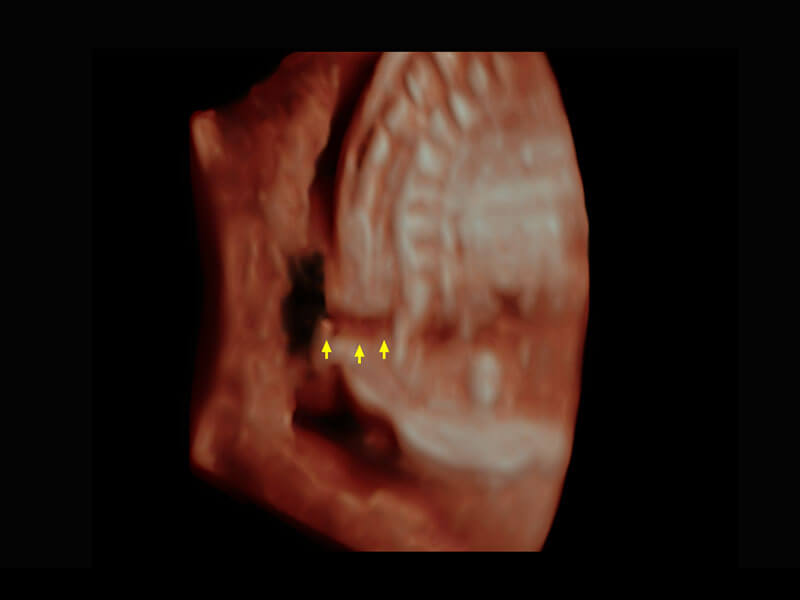

右室双出口

胎心容积成像